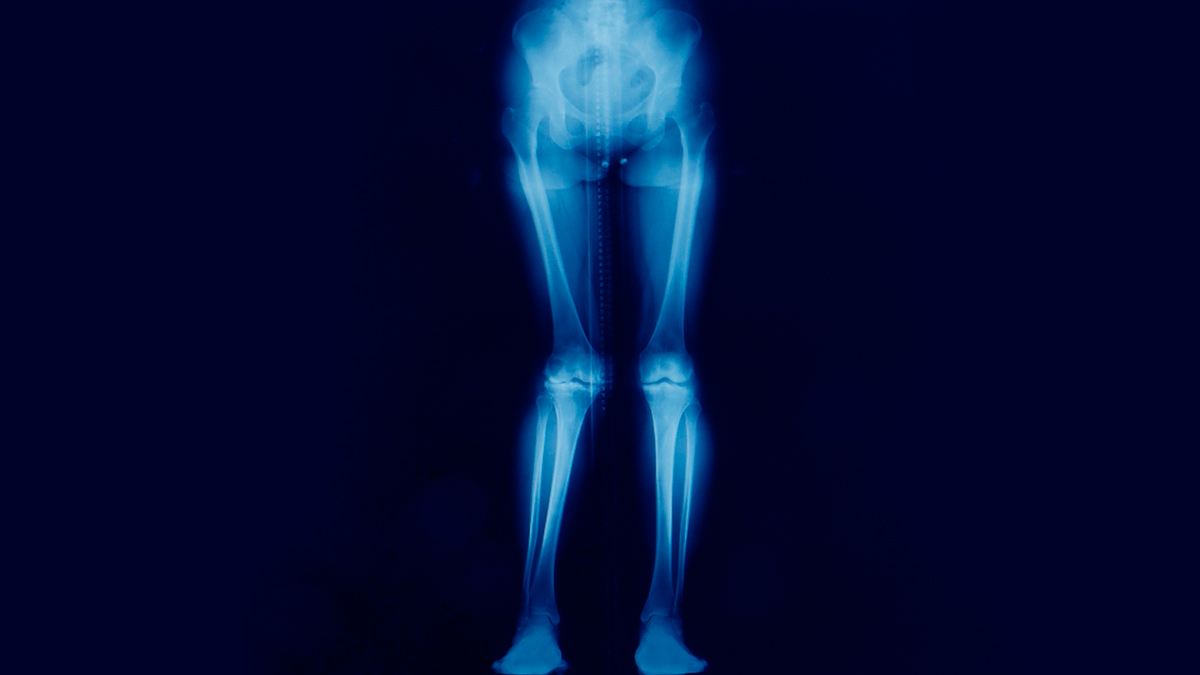

Dr Mahajan explained, “Knock knee, or genu valgum, is a condition where the knees bend inward and touch or 'knock' against each other, even when standing with the ankles apart. This misalignment puts excessive pressure on the outer side of the knee, potentially leading to pain and long-term damage.”

According to Dr Mahajan, most newborns typically have bowed legs (varus angulation). As the infant begins to stand and walk, the bowing may become more noticeable. This condition, known as physiologic genu varum (bowlegs), gradually improves, and by 18-24 months, the child usually attains neutral alignment (straight legs).

“Valgus or knock knees alignment of the lower extremities is normal in children between the ages of 2 and 8 years. The maximal amount of physiologic valgus occurs between the ages of 2 and 4 years, after which the alignment of the lower extremity assumes a mild valgus, the normal alignment in an adult,” Dr Mahajan said. Therefore, by 8 years old, there should be little or no change in the alignment of the lower extremity.